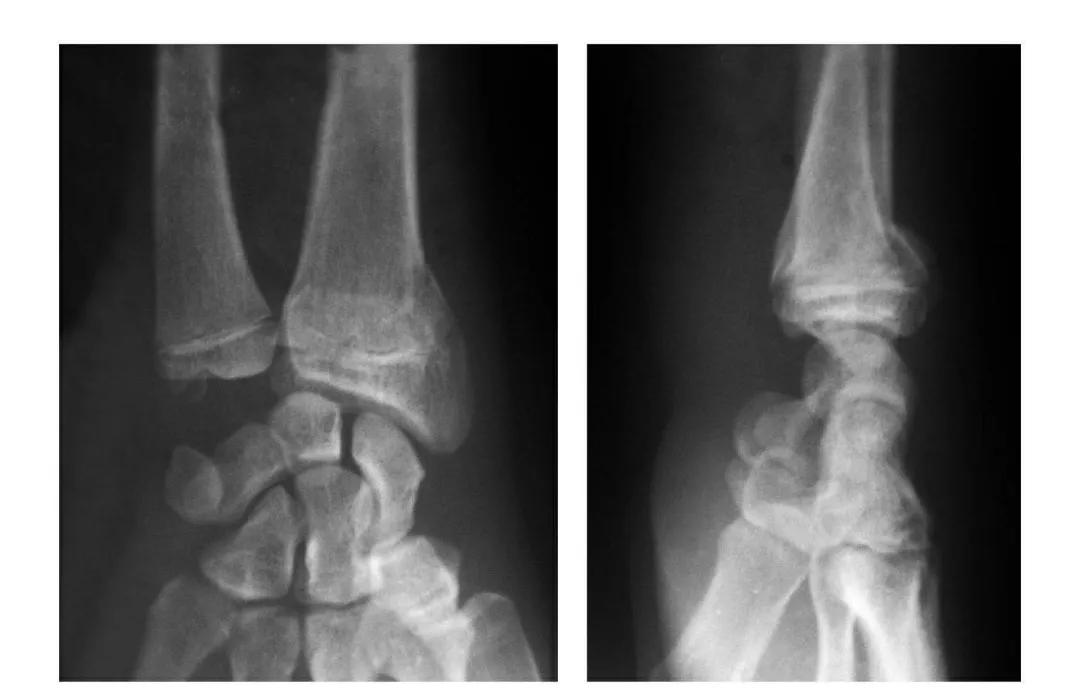

桡骨颈骨折(歪戴帽)

本病即桡骨小头骨折后关节面向外呈不同程度的倾斜。

例1:桡骨颈骨折后关节面向外倾斜50°。

例2:桡骨颈骨折后关节面向前外方呈130°倾斜移位。